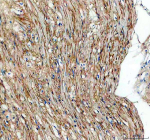

TGFBI Antibody (F44993)

Image F44993-0.4ML In 1X PBS, pH 7.4, with 0.09% sodium azide 0.4 ml 429